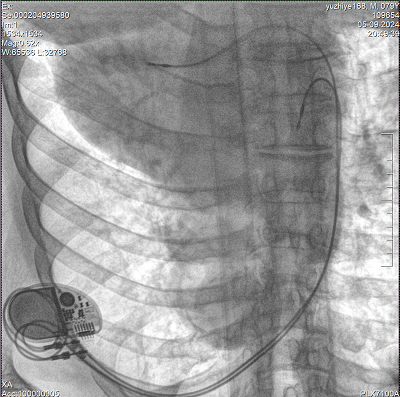

具備血管造影及數(shù)字減影(DSA)、路徑圖(Road-map)、透視、攝影等功能。 廣泛適用于介入科、血管外科、腫瘤科、消化內(nèi)科及骨科等多個(gè)臨床科室,典型應(yīng)用包括:TACE(肝腫瘤栓塞與化療灌注術(shù))、心臟起搏器置入術(shù)、四肢動(dòng)脈造影術(shù)、下肢靜脈濾器置入術(shù)、ERCP(經(jīng)內(nèi)鏡逆行胰膽管造影術(shù))等。

核心DSA軟件可實(shí)時(shí)生成高清血管影像,結(jié)合路徑圖功能,在手術(shù)中為醫(yī)生提供血管導(dǎo)航。